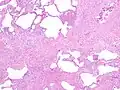

The histologic hallmarks of UIP, as seen in lung tissue under a microscope by a pathologist, are interstitial fibrosis in a "patchwork pattern", honeycomb change and fibroblast foci (see images below).[6] [7]

Appearance of honeycomb change in a surgical lung biopsy at low magnification. The dilated spaces seen here are filled with mucin. Hematoxylin-eosin stain, low magnification.